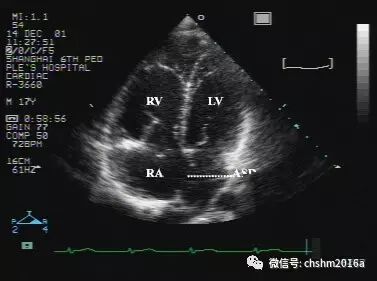

图2.3.1   心尖四腔观显示房间隔中断,右房、右室扩大

ASD:房间隔缺损   RA:右房   RV:右室   LV:左室